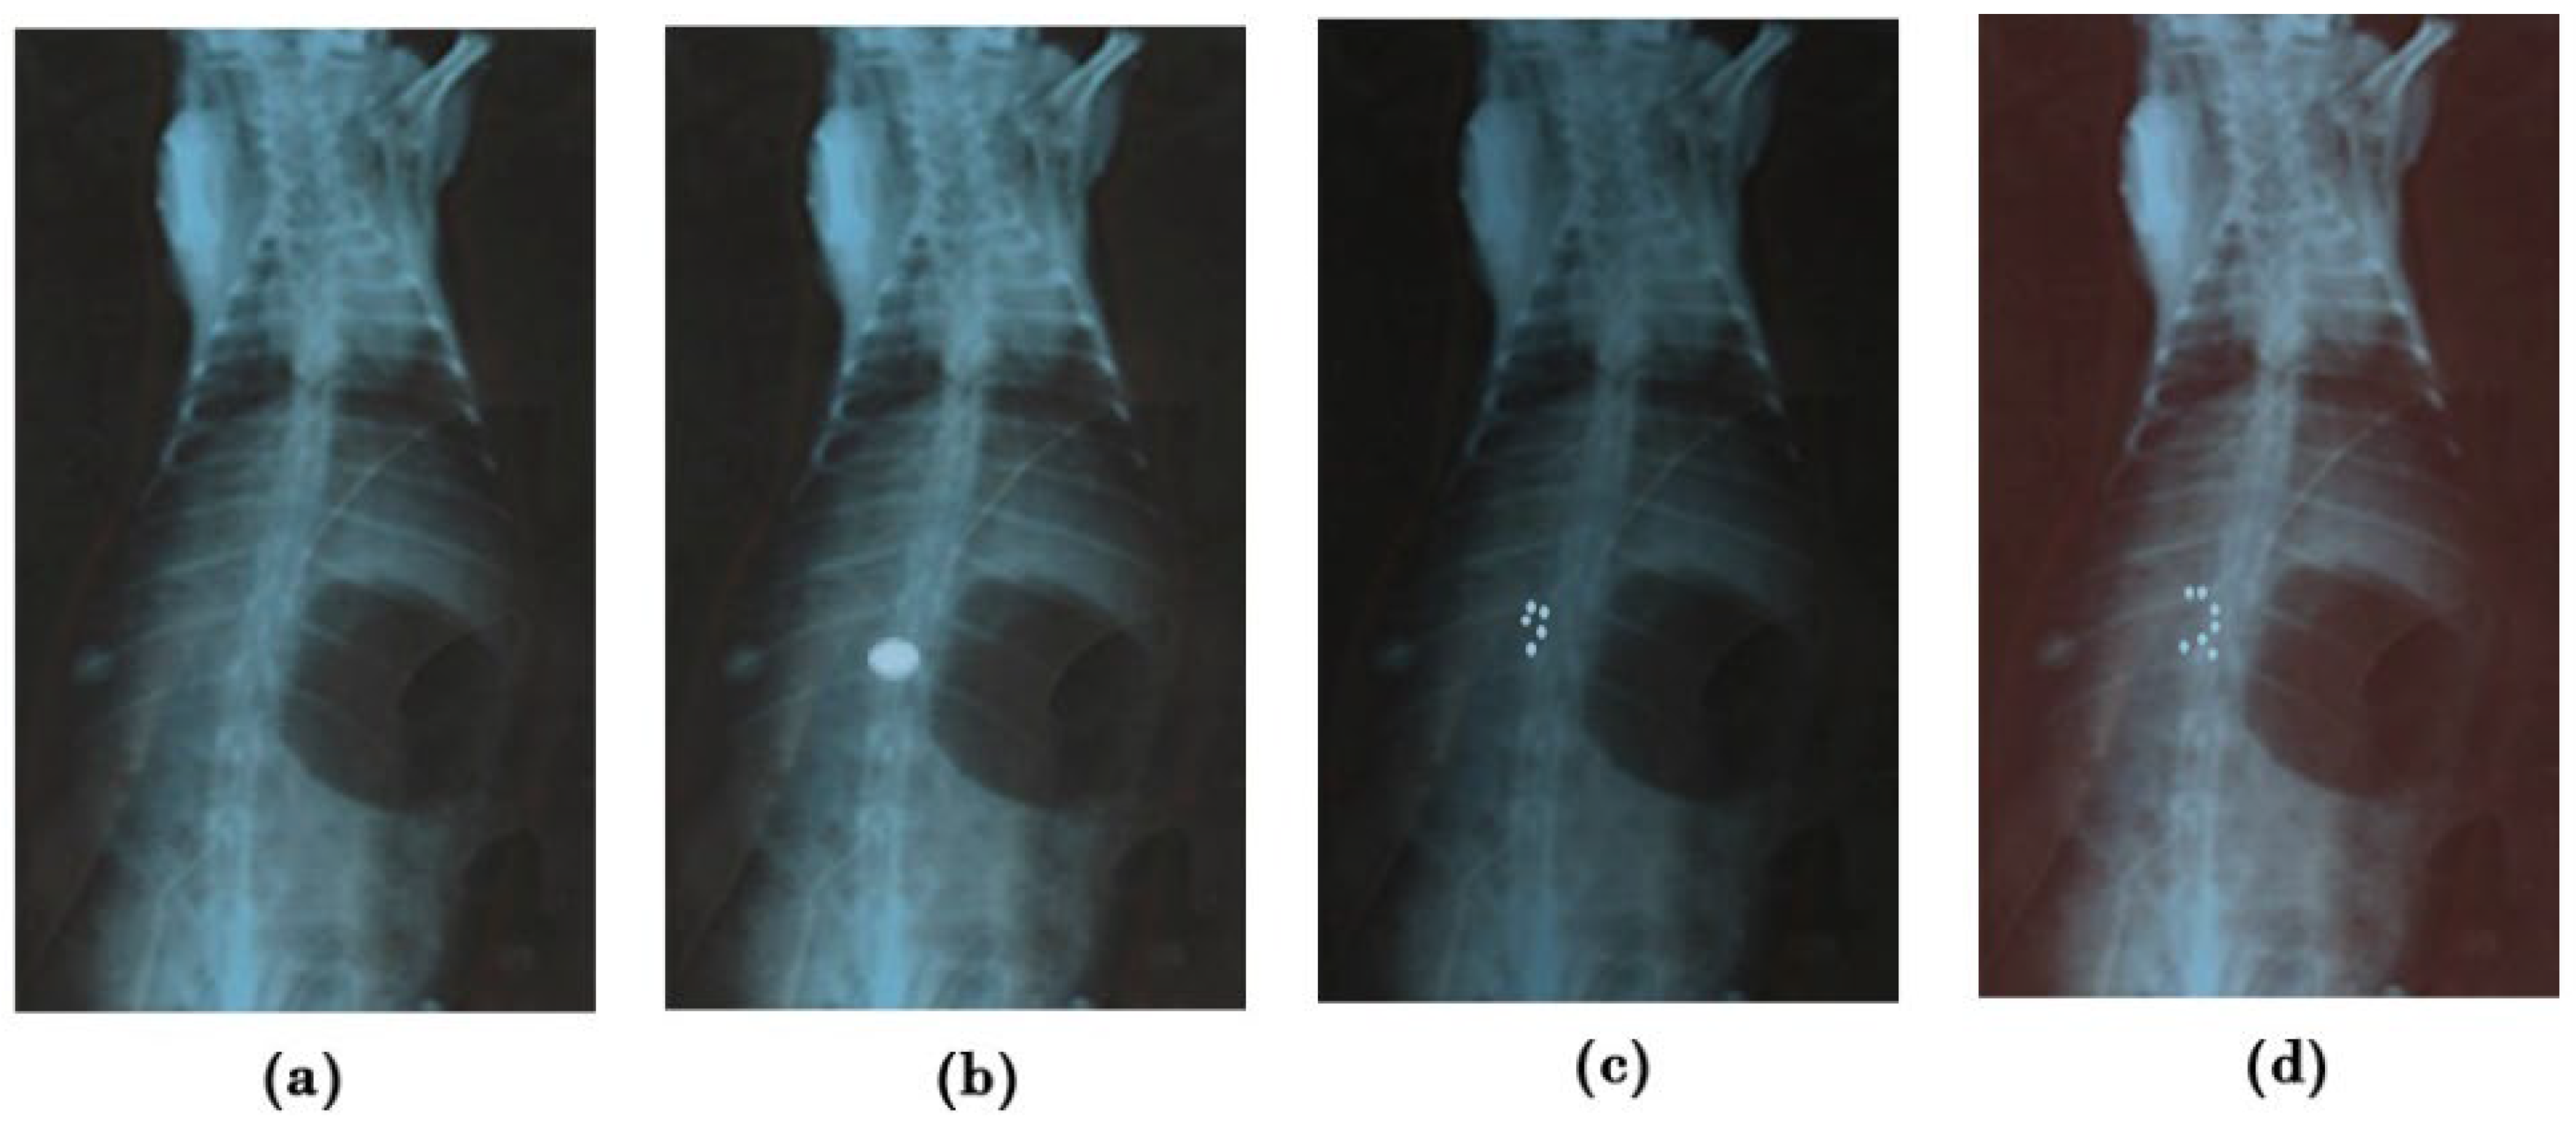

2.6. In Vivo Mucoadhesion Studies

3.9.1. In Vivo Mucoadhesion Study